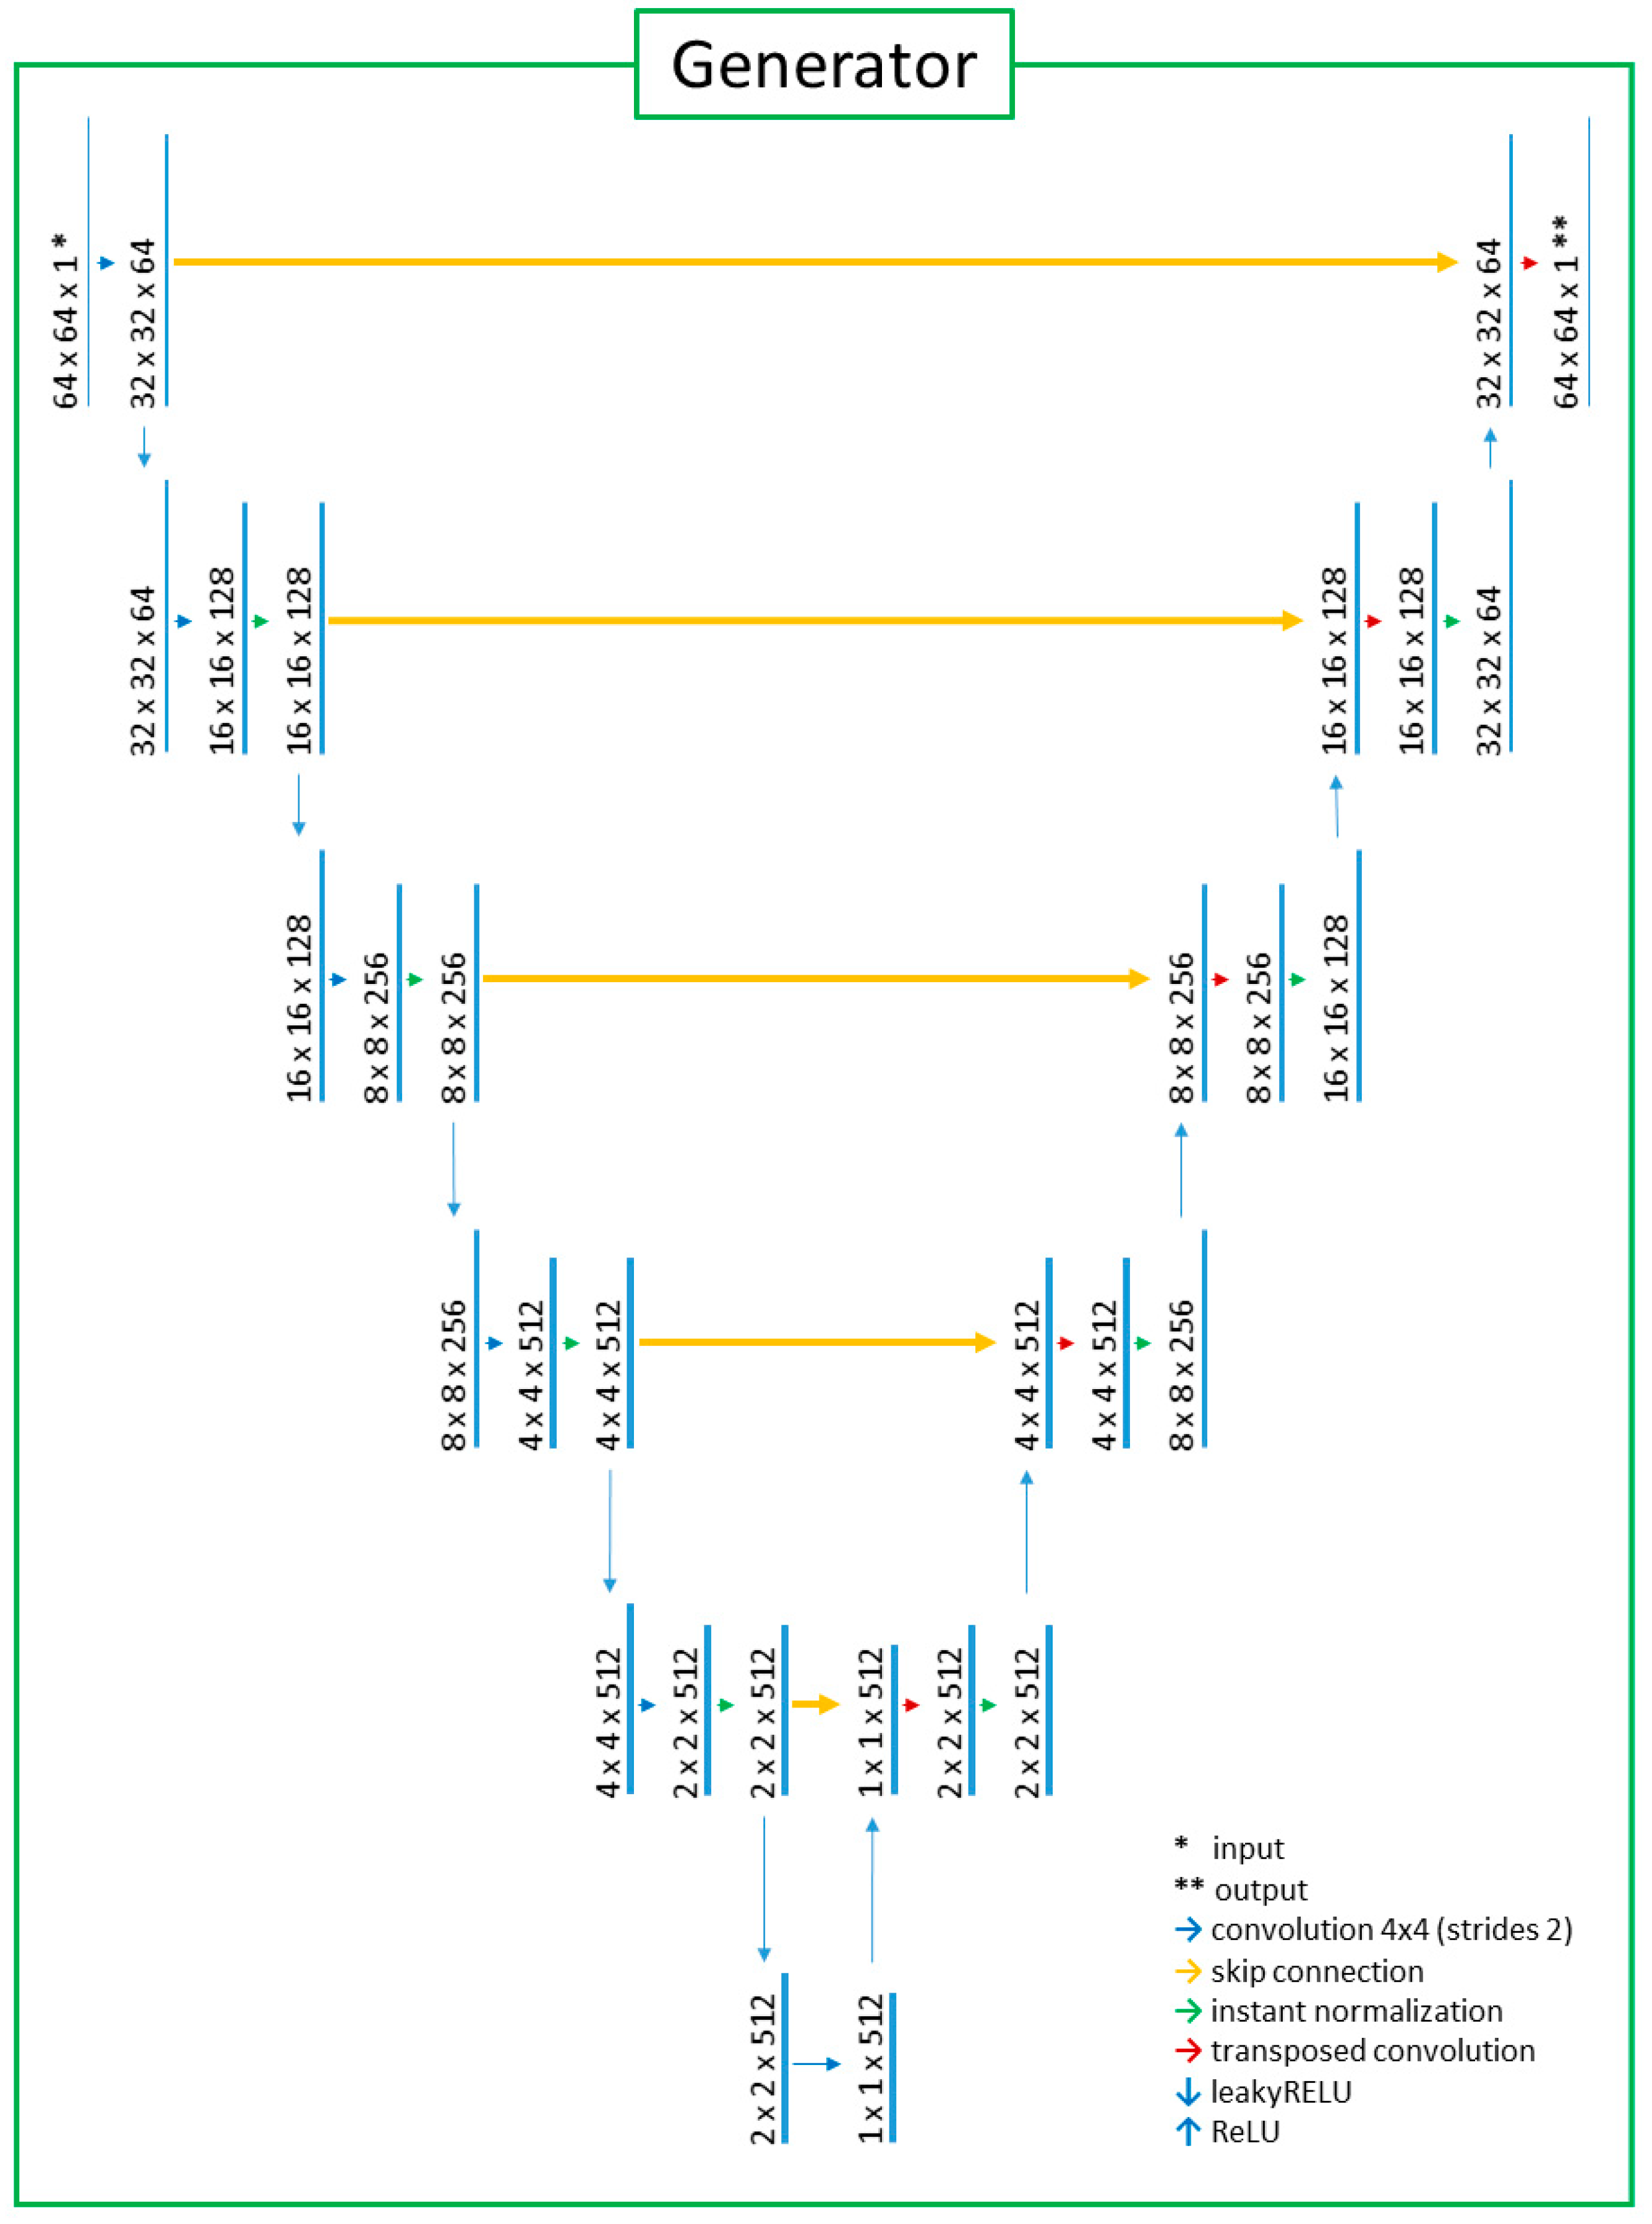

2.2. Deep-Learning Model with Image Preprocessing